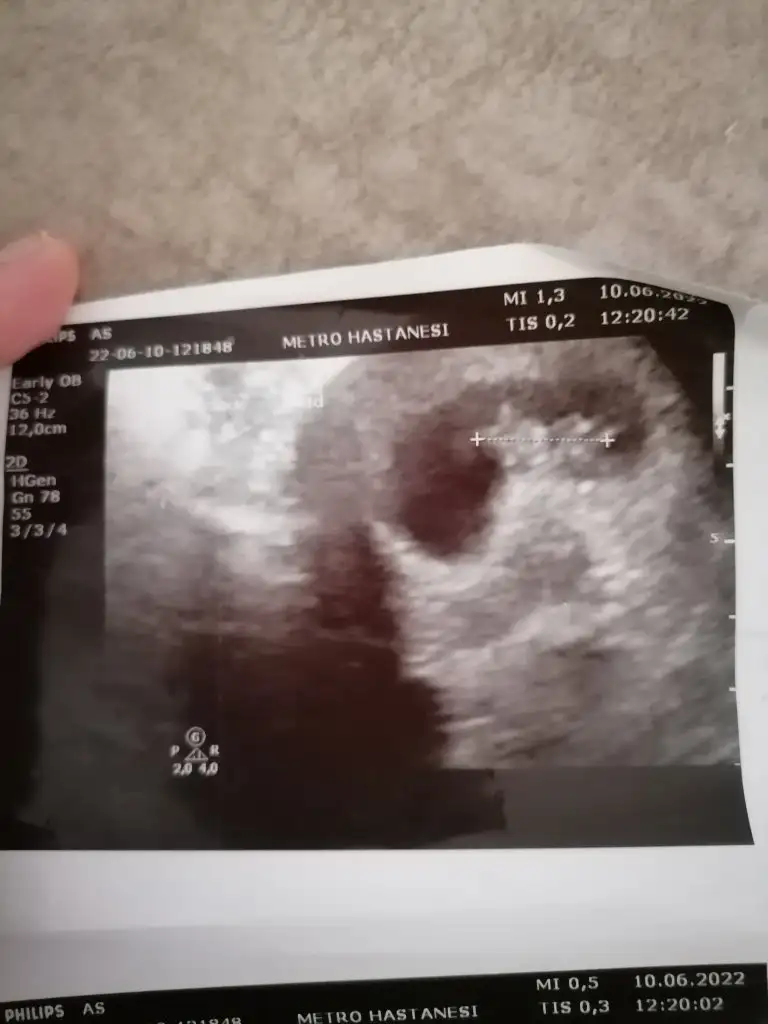

Çok teşekkür ederim doktor da erkeğe benziyor dedi ama kesin konuşmadı 3 hafta sonra netleşecek inşallah

inşallah 2 tane kızım var.bu da paşa olursa sevinirim.cevap için teşekkürler.belli olunca haber vericem :)paşa gibi

Hayırlısı bakalım 2 kızım var teşekkürlerprenses gibi